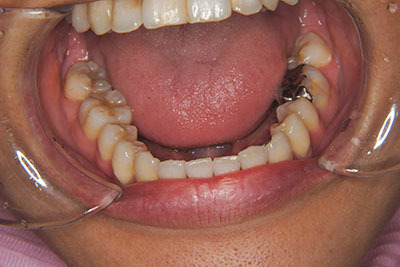

おとなの方でも矯正治療をあきらめないでください!

いくら歯が動き易くとも、本人がやる気でなければ効果は出ませんし、むし歯発生のリスクも高まります。おとなの方は顎の成長が終わっているため、治療の計画が立てやすいとも言えます。「もう大人だから…」とあきらめず、一度ご相談ください。